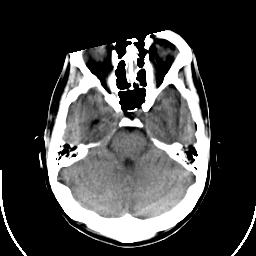

Sarcoma: Roentgen-ray CT -- Slice #7

[Home][Help][Clinical] Slice 7